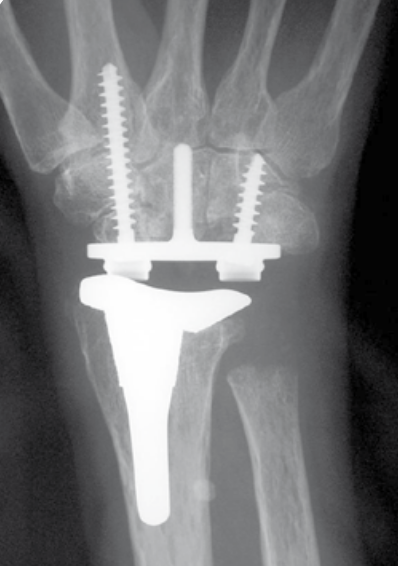

Total wrist arthroplasty

Indications

Low demand patient

Intact wrist extensors

Good bone stock

Technique

Universal TWAUniversal 2 TWA

Universal 2 Total Wrist Implant system surgical technique PDF

Dorsal approach

- incision in line with 3rd meta-carpal

- divide extensor retinaculum over ECU compartment and reflect radially

- mobilize entensor tendons

- ensure ECRB and ECRL intact

- elevate wrist capsule as a distally based flap

TWA

- uncemented radial prosthesis

- excise lunate and apply carpal cutting block to capitate

- cut 1 mm hamate / capitate head / midscaphoid

- screw fixation of carpal plate

- trial polyethylene component

Results

Wagner et al CORR 2017

- 425 primary total wrist arthroplasty followed for mean 2 years

- 90% inflammatory arthritis

- intra-operative fractures 2%

- postoperative fractures 2%

- 88% 10 year survival